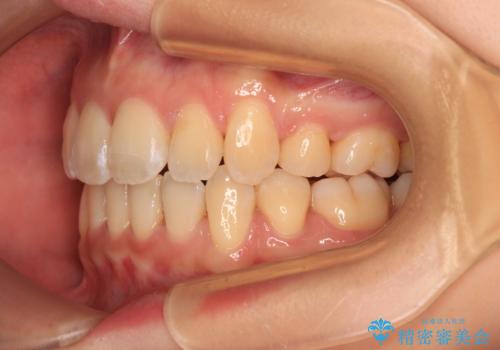

- 前歯の出っ歯と口元の閉じにくさを気にして来院された患者様です。

口元を積極的に引っ込めるために、上下左右の小臼歯4本を抜歯し、目立たないワイヤー装置にて矯正治療を行うこととしました。

上下前歯の歯軸の角度が大きく改善され、お口を閉じたときに顎先に認められた梅干し様の皺も改善されました。